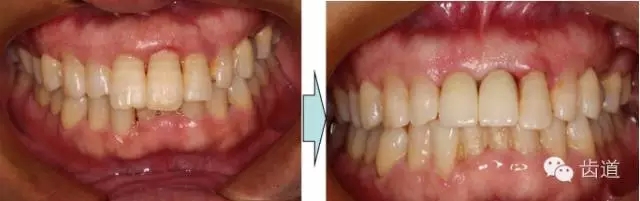

治療前后對(duì)比

戴牙半年后復(fù)查

戴牙一年前后對(duì)比

本病例為前牙外傷致根折,牙周無(wú)明顯炎癥,唇側(cè)骨板厚度大于1mm且根方骨量充足,適合即刻種植。術(shù)前簡(jiǎn)易導(dǎo)板的制作以及術(shù)中牙周探針精確的測(cè)量,保證了種植體的三維位置及軸向均按標(biāo)準(zhǔn)的即刻種植手術(shù)進(jìn)行。術(shù)后參考拔除牙齒的頸部形態(tài)制作個(gè)性化愈合基臺(tái),實(shí)現(xiàn)了對(duì)牙齦塑型的早期干預(yù),打破了傳統(tǒng)二期牙齦成型的做法,所成型的牙齦袖口與之前的天然牙相似,有利于維持牙齦形態(tài)的穩(wěn)定和美觀。